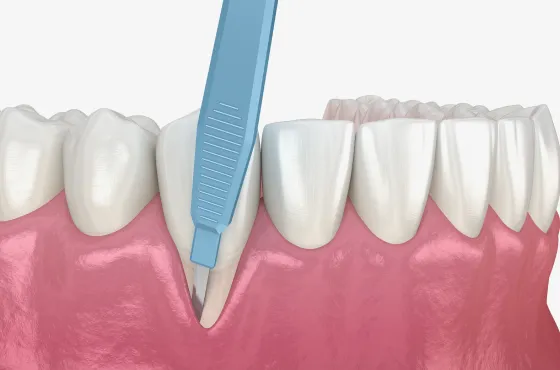

下がった歯茎を美しく、強く再生|

30代 男性

矯正治療と根面被覆術による口腔環境の改善

治療名 【審美・機能回復】歯肉退縮に対する根面被覆術+マウスピース矯正 治療期間 約1年 執刀医 Dr. 大杉 治療費 1,150,000円(税込)

■内訳:

矯正治療 900,000円

オペ費用 250,000円治療解説 歯肉退縮の改善と、将来的に歯を失うリスクを下げる目的で治療を行いました。

まずマウスピース矯正で歯列と噛み合わせを整えたうえで、結合組織移植による根面被覆を実施。

見た目だけでなく、歯を長く残すための安定性も重視して回復を図りました。リスク・副作用 歯の移動時に数日程度の違和感や疼痛が生じることがあります。

術後の過度なブラッシング圧や不適切な清掃用具の使用は、再度の歯肉退縮(再発)を招く主原因となるため、適切なケア指導の遵守が必要です。 -